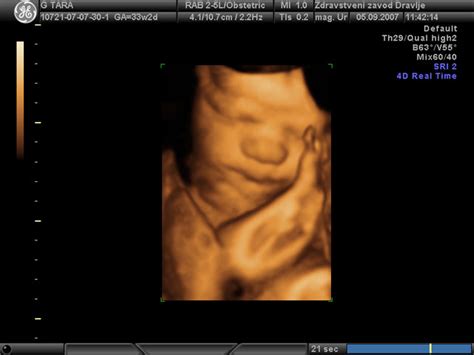

Eden izmed prvih opaznih znakov, da se porod bliža, je t.i. zagozditev ali "spuščanje" otroka. To se zgodi, ko se spodnji del maternice zmehča in razširi, omogočajoč otrokovi glavici, da se spusti niže v medenico. Pri ženskah, ki prvič rodijo, se ta pojav običajno zgodi 2 do 4 tedne pred začetkom popadkov. Pri ženskah, ki že imajo otroke, se zagozditev pogosto zgodi tik pred samim porodom.

Ta premik navzdol prinaša olajšanje v smislu dihanja, saj se pritisk na pljuča zmanjša. Prav tako se lahko drugi simptomi nosečnosti, ki so bili prej moteči, umirijo. To je naraven proces, ki nakazuje, da se telo aktivno pripravlja na veliki dogodek.